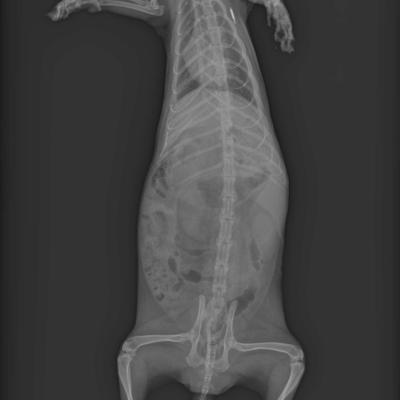

Corps entier de Furet